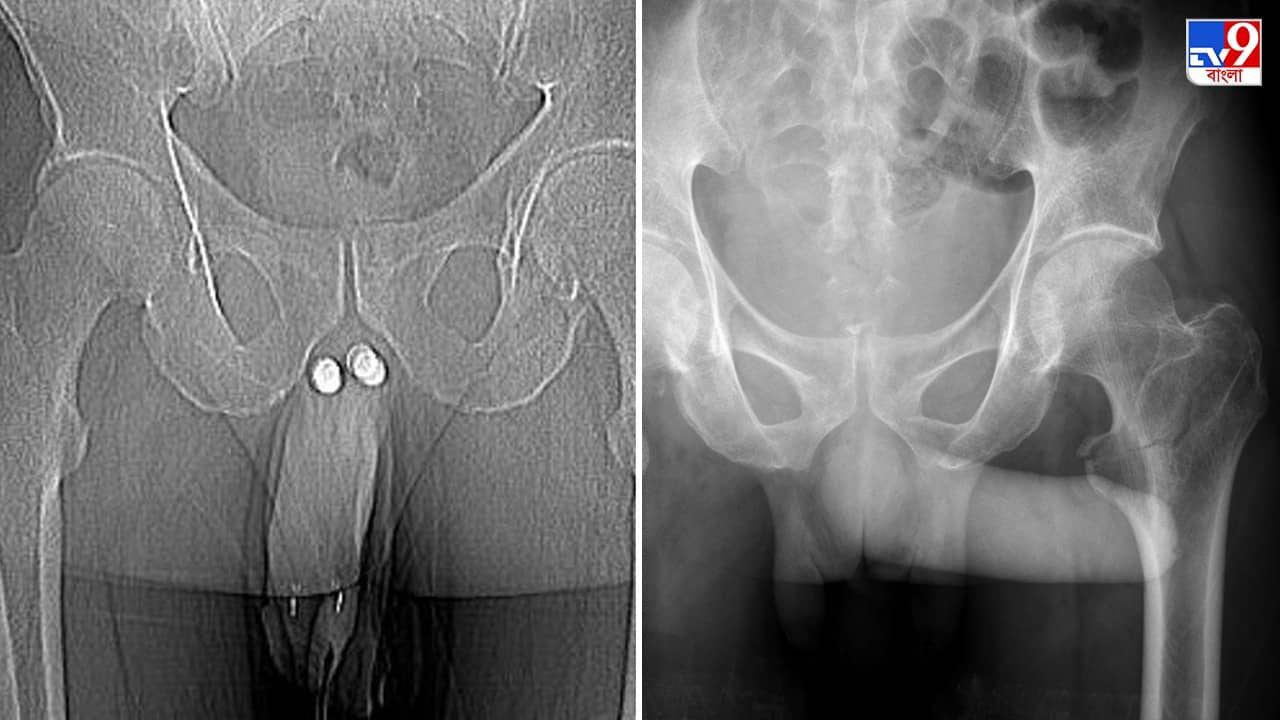

এমন ঘটনা সচরাচর শোনা যায় না। সম্প্রতি ইন্দোনেশিয়ার এই ব্যক্তির সঙ্গে ঘটে গিয়েছে এমন দুর্ভাগ্যজনক ঘটনা। স্ত্রীর সঙ্গে যৌন মিলনের সময় যৌনাঙ্গ ভেঙে গেল এই ব্যক্তির। সঙ্গমের (sexual intercourse) সময় পেনাইল ফ্র্যাকচারের এই ঘটনা চিকিৎসা পরিভাষায় Eggplant Deformity নামে পরিচিত। এই রোগকে বিরল রোগ হিসেবেই দেখছেন বিশেষজ্ঞরা। ইন্টারন্যাশনাল জার্নাল অফ সার্জারি-তে এই ঘটনার উল্লেখও রয়েছে। ৫০ বছরের বয়সী ওই ব্যক্তি যেমন জানিয়েছেন, স্ত্রীর সঙ্গে সহবাস করার সময় তাঁর লিঙ্গে ফাটল অনুভব করেছিলেন। এরপর প্রায় চার ঘন্টা ধরে তাঁর যৌনাঙ্গ ফুলে ছিল। সেই ব্যথা আর জ্বালা ভাব তো ছিলই। এরপর তাঁর ইরেকশন বন্ধ হয়ে যায়। সেই সঙ্গে মূত্রনালীতে রক্তক্ষরণ শুরু হয়। সঙ্গে বীর্যপাতও বন্ধ হয়ে যায়। পরবর্তীতে দেখা যায়, তাঁর লিঙ্গ বেগুনি রং ধারণ করেছে, সেই সঙ্গে স্ক্যানিং রিপোর্টে দেখা যায় লিঙ্গের ডানদিক বাজে ভাবে জখম হয়েছে। লিঙ্গ থেকে অন্ডকোষ পর্যন্ত রক্তজমে গিয়েছে। যে কারণে লিঙ্গ থেকে রক্তচলাচল বন্ধ হয়ে গেছে। সেই সঙ্গে মূত্রনালী ফেটে যাওয়াতে প্রস্রাবও বন্ধ হয়ে গিয়েছে। যে কারণে অতি দ্রুত চিকিৎসা শুরু করার প্রয়োজন ছিল।

গবেষণায় বলা হয়েছে, পরীক্ষায় এই গোলযোগ ধরা পড়লে দ্রুত অপারেশনের উদ্যোগ নেওয়া হয়। পুনরায় লিঙ্গকে সচল করার জন্য প্রথমে লিঙ্গ খুলে ফেলা হয়। এরপর লিঙ্গের ভিতর জমে থাকা লিক্যুইড আর রক্ত পরিষ্কার করে ক্ষতিগ্রস্ত মূত্রনালী এবং পেনিসের কোষ পুনর্গঠন করা হয়। এরপর কৃত্রিমভাবে তার ইরেকশন করানো হয়। পেনাইল ফাংশন পরীক্ষা করে দেখা হয় বার বার। অপারেশনের পাঁচ দিন পর ইরেকটাইল পরীক্ষায় ভাল ফল আছে তার। এরপর তাঁকে চিকিৎসকরা ছেড়ে দেওয়ার সিদ্ধান্ত নেন। তবে টানা ২১ দিন ক্যাথিটার পরানো ছিল। ওর মাধ্যমেই ইউরিন পাস করত। নিয়মিত ভাবে ফলো-আপ করার ৪ মাস পর চিকিৎসকেরা দেখলেন, বীর্যপাতে কোনও রকম সমস্যা না হলেও লিঙ্গ একদিকে কিছুটা বেঁকে রয়েছে। তবে তা সমস্যার কিছুই নয়, ওই ব্যক্তি নিরাপদ যৌন মিলনে সক্ষম বলে আশ্বস্ত করেছেন চিকিৎসকেরা।